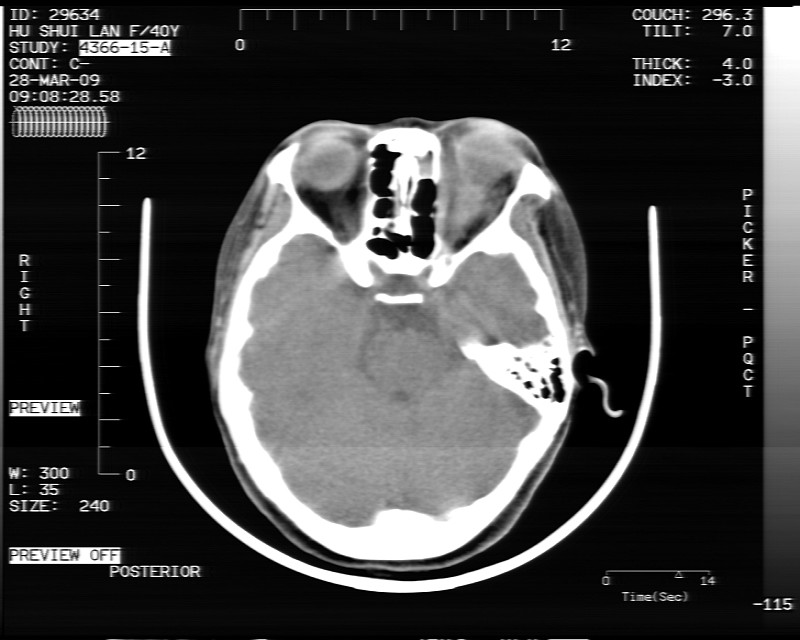

女性,40岁,左眼疼痛,视力模糊,五年曾行左眼脂肪瘤手术。

患者现病史不知持续有多久了,现片示眶内病灶边缘较模糊,眶脂混浊,多考虑炎性假瘤,不除外肿瘤

1)左眼眶内占位性病变,性质待定(不排除炎性假瘤);建议行进一步检查。2)左侧额窦炎。